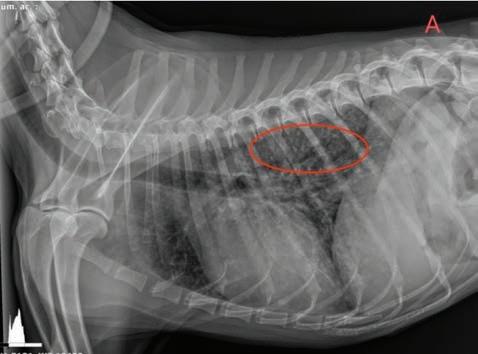

Se realizó una angio-TC de la cavidad torácica para caracterizar la masa mediastínica craneoventral. El estudio se realizó bajo anestesia general y con la paciente en decúbito esternal. Se realizaron series precontraste y post-contraste, inmediatamente y a los 3 minutos tras la administración de un contraste iodado hidrosoluble no iónico (iopromida 300 mg I/ml a una dosis de 600 mg I/kg intravenoso, administrado de forma manual) con cortes de 3 mm de grosor e intervalo 1,5 mm con algoritmo estándar (tejido blando) y pulmón. El estudio de TC se evaluó en ventana de tejido blando, hueso y pulmón, visualizándose en el área craneal al atrio derecho una estructura redon-

deada y bien definida (22UH) de medidas aproximadas 1,95 cm DV x 1,87 CrCd x 2,5 cm LL (Figs. 4 y 5). Tras la administración de contraste, esta estructura se llenó rápidamente de contraste de forma homogénea,

Figura 4. Imágenes de Tomografía Computarizada. Reconstruidas en plano sagital, simples (A) e inmediatamente tras la administración del contraste (B), en plano transversal, simples (C).

observándose una comunicación con el atrio derecho, midiendo el área de la comunicación 1,43 cm. El diagnóstico presuntivo fue de un aneurisma de la aurícula derecha.